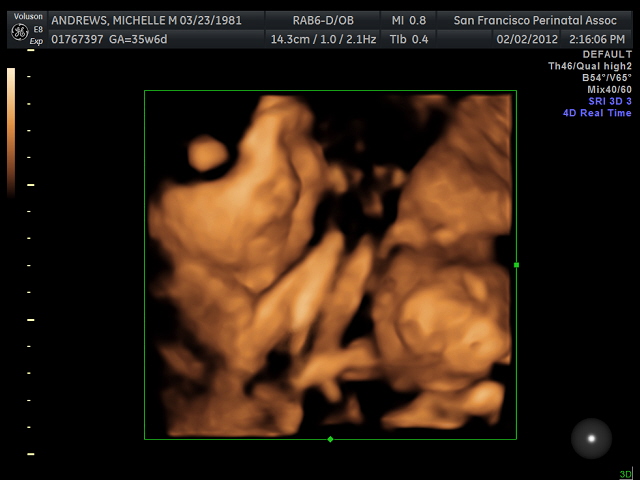

Ultrasound day! I am super excited. Pictures to follow...

At least he's consistent; Ezra hid from the ultrasound tech so we only got two partially decent images...

I like his Phantom of the Opera impression in the first image, and I die for those cheeks!! The doctors estimate that he weighs 7 pounds, 2 ounces at this point. My doctor hopes that I go into labor at least a week early, but I'm not yet dilating. However, my cervix has "thinned out" and Ezra's head is right on it, so she believes it's possible I may deliver well before the due date.